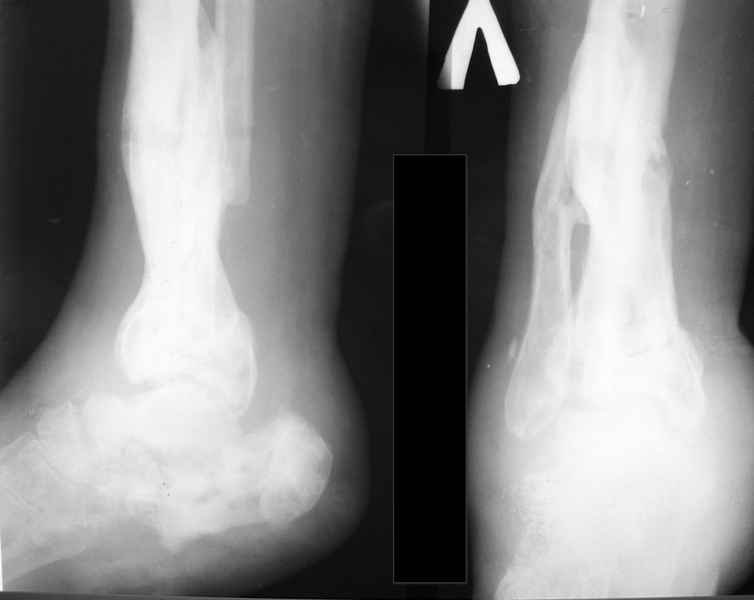

Молодая девушка со сросшимися многооскольчатыми переломами пяток и голеней.Young girl with fractures of the calcaneus Больная Н., 25 лет, падение с высоты (2008 г.). Жалобы на боли в области голеностопных суставах, в области пяток при ходьбе. Лечилась в аппаратах внешней фиксации по поводу открытых оскольчатых переломов обеих голеней, переломов пяток. Далее по поводу несросшихся переломов голеней –ЧКОС аппаратами внешней фиксации. Переломы срослись, аппараты демонтированы весной 2010г. В левой пяточной области в месте проведения спицы имеется сукровичное отделяемое. При ревизии гноя нет. Чем помочь девушке?

Patient N., age 25, falls from heights (2008). Complaints of pain in the ankles, in the heel when walking. She was treated by external fixation on open comminuted fractures of both legs, fractures of the calcaneus. Then she was treated by external fixation from nonunion of both legs. Now fractures are fused, apparatuses removed in the spring of 2010. How to help a girl?